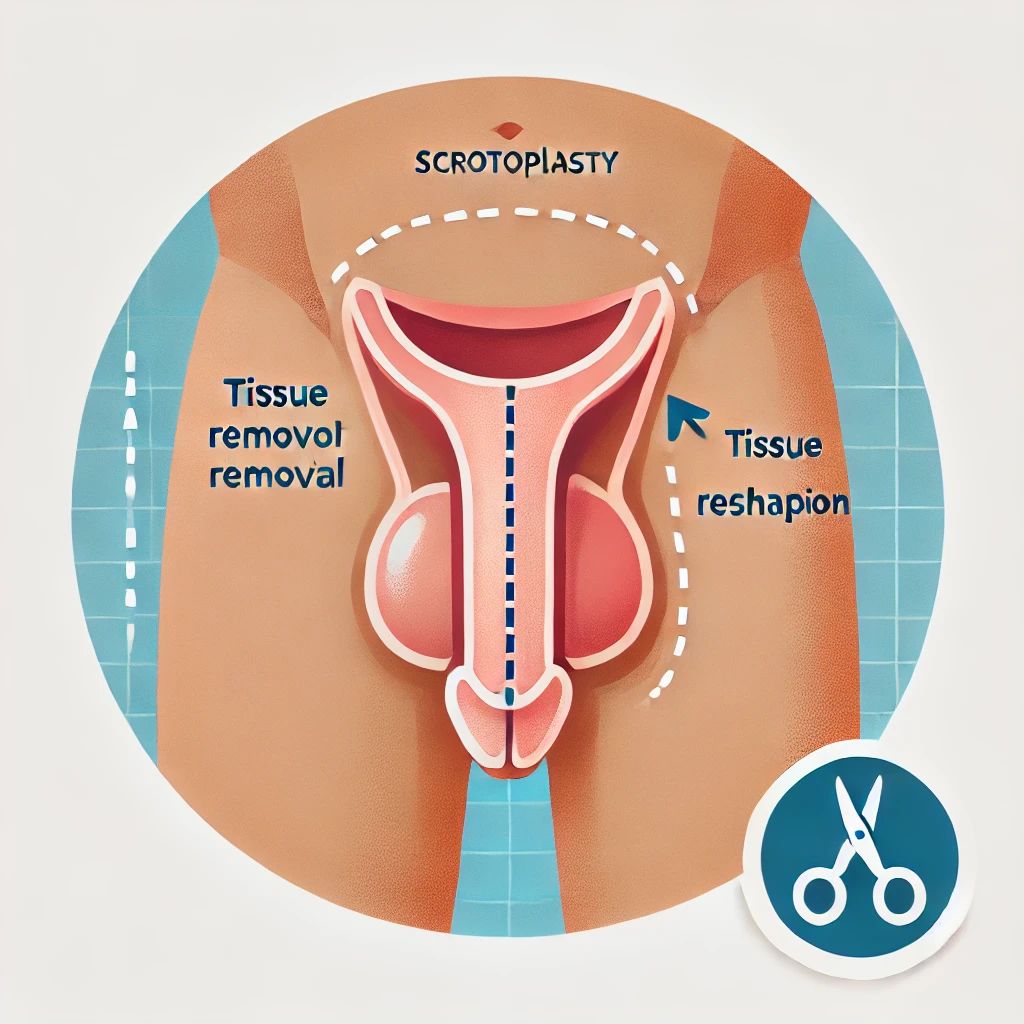

مقالات طبية من مساهمات الأطباء

أطباء التجميل في تركيا

42 listings